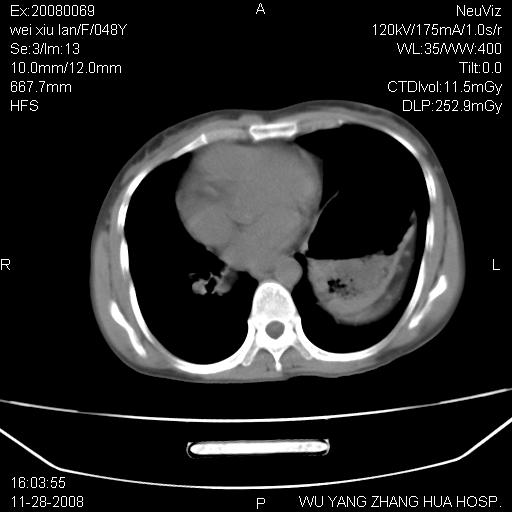

标题: CT16847:女,48岁,咳嗽,发热两日,平常偶有上腹部不适。 [打印本页]

标题: CT16847:女,48岁,咳嗽,发热两日,平常偶有上腹部不适。

能否考虑食管裂孔疝?请老师们多多指教。

支持左侧膈疝,心脏受压右移.

胃、脾脏及部分肠管明显升高,并压迫心脏移位,

首先考虑:左侧膈疝。

左侧胸腔内见胃肠及脾脏影

支持膈疝